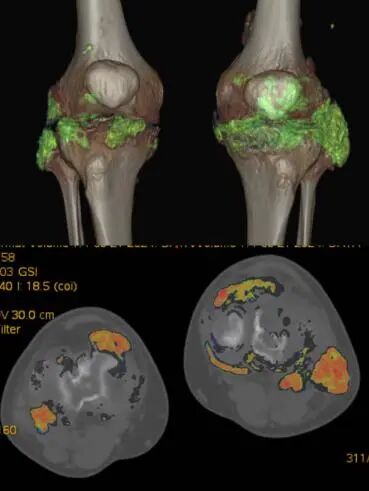

更精準(zhǔn)——能譜CT掃描

設(shè)備利用能譜技術(shù),可實現(xiàn)同時、同向、同源瞬切及靈活多物質(zhì)定性定量,進而獲得腫瘤病灶密度和成分的微小差別,在早期診斷病灶和實現(xiàn)精準(zhǔn)腫瘤分期及療效評估方面具有顯著優(yōu)勢。

該設(shè)備還能利用能譜掃描更好地去顯示組織結(jié)構(gòu),提高小病灶的檢出率,提高靜脈成像質(zhì)量,消除金屬偽影,反映組織器官病變的特點和規(guī)律等。